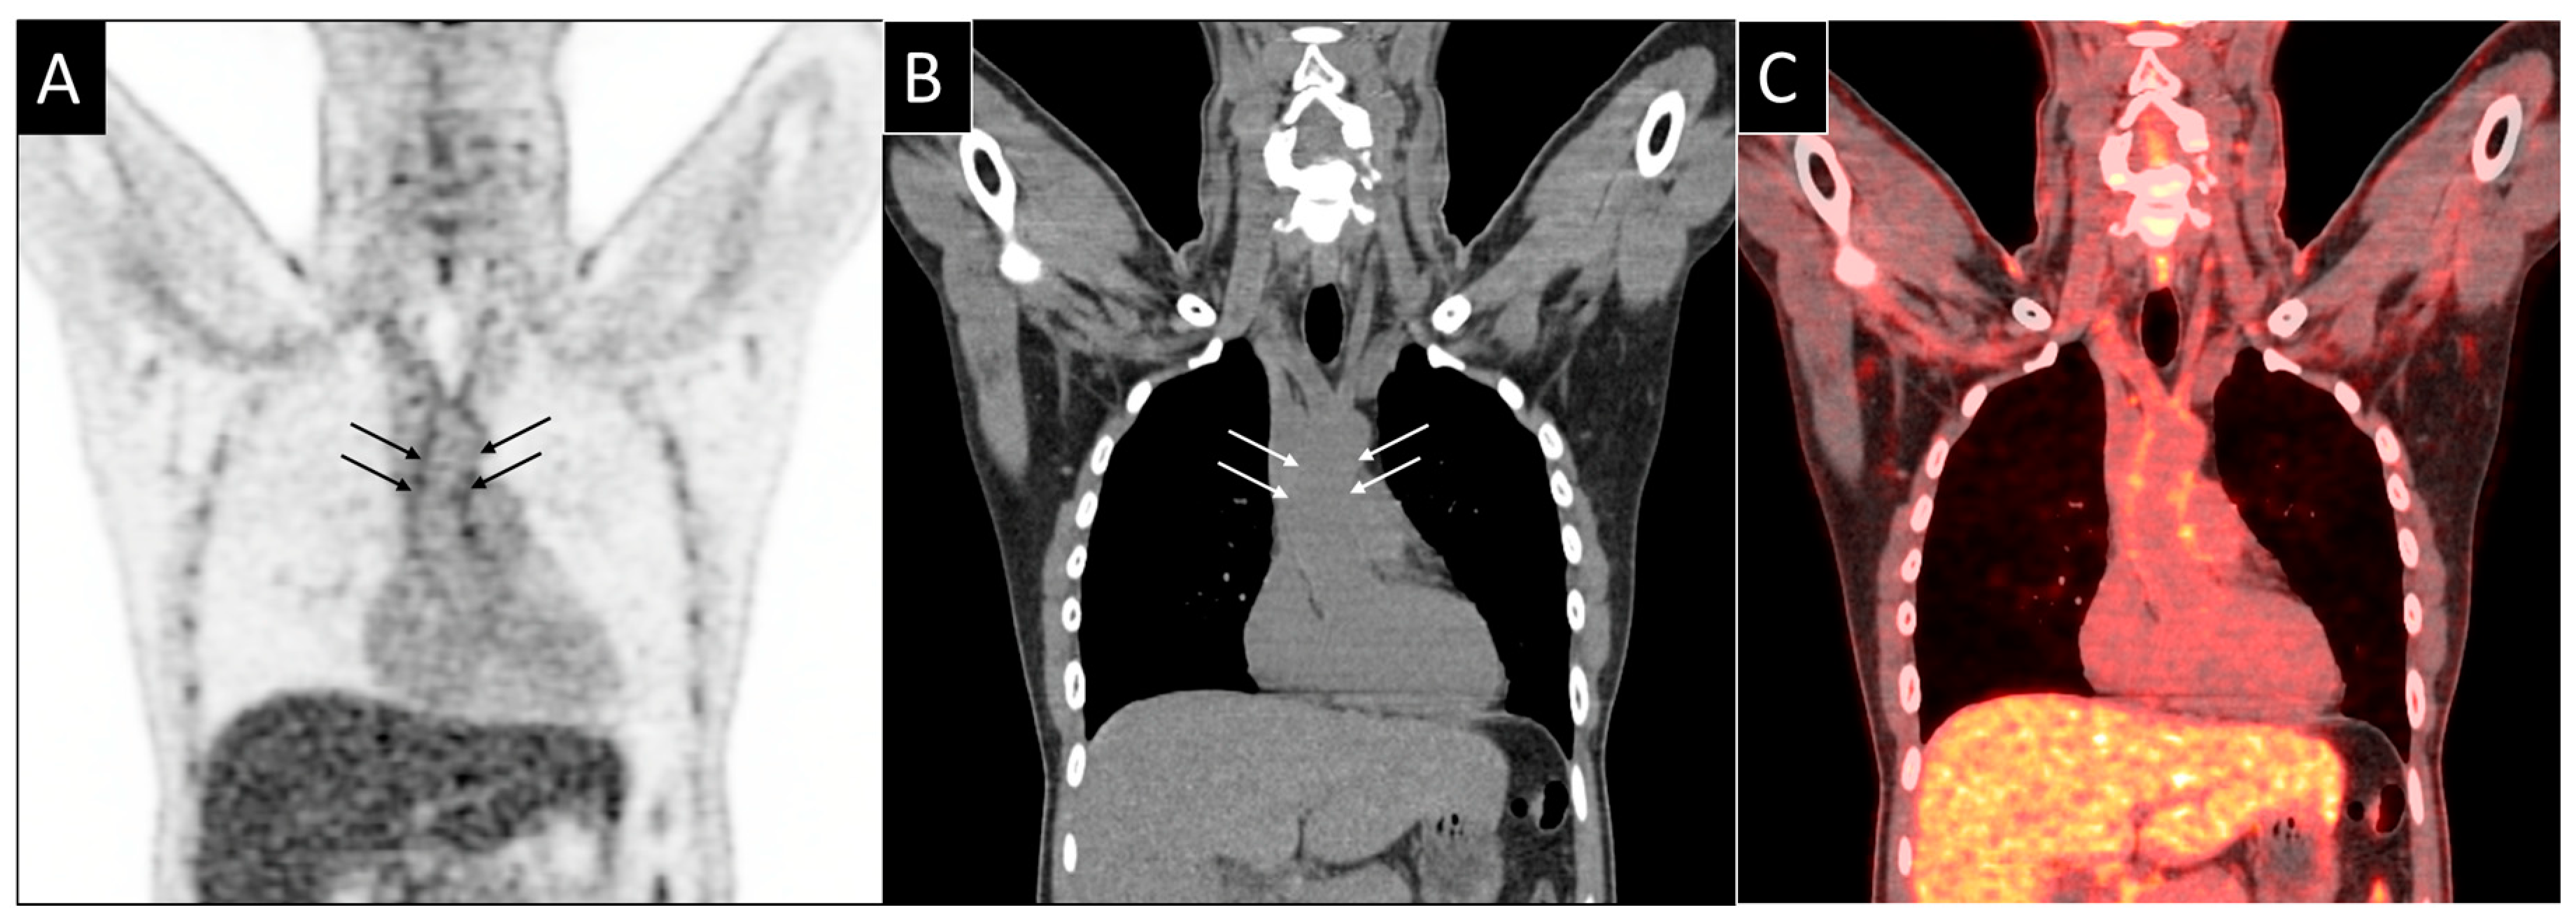

6. 18F-Fluorodeoxyglucose Positron Emission Tomography (FDG PET)

- Jiemy, F.W.; Heeringa, P.; Kamps, J.A.A.M.; van der Laken, C.J.; Slart, R.H.J.A.; Brouwer, E. Positron emission tomography (PET) and single photon emission computed tomography (SPECT) imaging of macrophages in large vessel vasculitis: Current status and future prospects. Autoimmun. Rev. 2018, 17, 715–726. [Google Scholar] [CrossRef]

- Longenecker, C.T.; Sullivan, C.E.; Morrison, J.; Hileman, C.O.; Zidar, D.A.; Gilkeson, R.; O’Donnell, J.; Mc Comsey, G.A. The effects of HIV and smoking on aortic and splenic inflammation. AIDS 2019, 32, 89–94. [Google Scholar] [CrossRef]

- Lawal, I.O.; Ankrah, A.O.; Popoola, G.O. Arterial inflammation in young patients with human immunodeficiency virus infection: A cross-sectional study using F-18 FDG PET/CT. J. Nucl. Cardiol. 2018. [Google Scholar] [CrossRef]

- Zanni, M.V.; Toribio, M.; Robbins, G.K.; Burdo, T.H.; Lu, M.T.; Ishai, A.E.; Feldpausch, M.N.; Martin, A.; Melbourne, K.; Triant, V.A.; et al. Effects of Antiretroviral Therapy on Immune Function and Arterial Inflammation in Treatment-Naive Patients With Human Immunodeficiency Virus Infection. JAMA Cardiol. 2016, 1, 474–480. [Google Scholar] [CrossRef]

- Knudsen, A.; Fisker, M.; Loft, A.; Lebech, A.; Ripa, S. HIV infection and arterial inflammation assessed by 18 F-fluorodeoxyglucose (FDG) positron emission tomography (PET): A prospective cross-sectional study. J. Nucl. Cardiol. 2015, 22, 372–380. [Google Scholar] [CrossRef]

- Tawakol, A.; Lo, J.; Zanni, M.; Marmarelis, E.; Ihenachor, E.; MacNabb, M.; Wai, B.; Hoffmann, U.; Abbara, S.; Grinspoon, S. Increased Arterial Inflammation Relates to High-risk Coronary Plaque Morphology in HIV-Infected Patients. J. Acquir. Immune Defic. Syndr. 2015, 66, 164–171. [Google Scholar] [CrossRef]

- Yarasheski, K.E.; Laciny, E.; Overton, E.T.; Reeds, D.N.; Harrod, M.; Baldwin, S.; Dávila-román, V.G. 18FDG PET-CT PET-CT imaging detects arterial inflammation and early atherosclerosis in HIV-infected adults with cardiovascular disease risk factors. J. Inflamm. 2012, 9, 1–9. [Google Scholar] [CrossRef]

- Subramanian, S.; Tawakol, A.; Burdo, T.H.; Wei, J.; Corsini, E.; Hoffmann, U.; Williams, K.C.; Lo, J.; Grinspoon, S.K. Arterial Inflammation in Patients With HIV. JAMA 2012, 308, 379–386. [Google Scholar] [CrossRef]